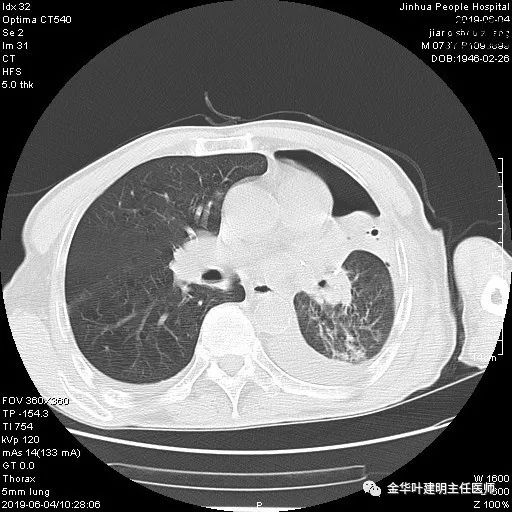

6.4上午:24小时引流出血性乳糜液1800毫升。是否再次手术进行右进胸胸导管结扎,抑或继续保守治疗非常纠结!压力非常大!!多方讨论会诊无法取得一致意见,但一般认为,引流量在1000毫升以上宜积极手术。情况与浙二医院范军强教授联系,请求指导,范教授认为左侧肺手术,损伤胸导管主干的机会较小,多数可保守治疗而愈。在他们的病例中,也有结扎胸导管后引流量仍无减少,效果并不能完全保证。建议可以考虑胸管夹管观察(因为淋巴管压力低,予以适当的压力,漏出量可能会明显减少),同时继续禁食,并静脉营养支持,引流管口可能会有渗液,注意更换敷料。与家属充分沟通后决定试夹管;这天血色素9.0 g/L;胸部CT复查示: